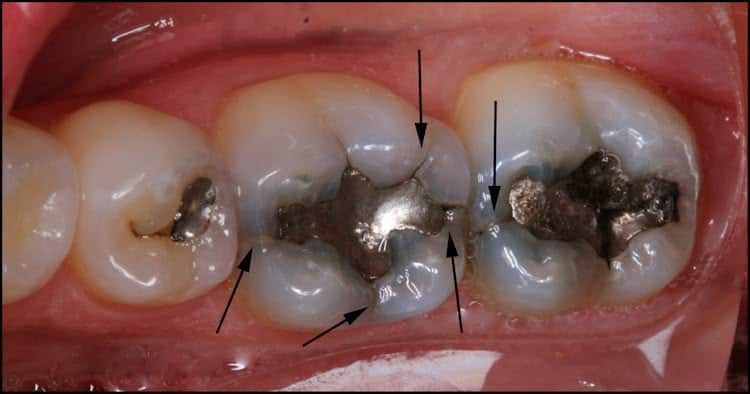

Research tells us that teeth with tooth-colored (composite resin) fillings crack just as often as those with silver fillings. My experience over 15 years, however, tells me that teeth with LARGE silver fillings crack much more frequently than with composite fillings. But even the bonding process can’t stop a crack from forming if the stress isn’t relieved. I’d like to show you some examples of what we often see:

It does seem that these cracks form around old fillings most of the time……..but they can even happen in teeth that have never had any work done. All it takes is a lot of force (usually grinding and/or clenching your teeth) and enough time. Here’s an example from a young man in his late 30’s who clenches his teeth so hard that he split this back molar completely in 1/2. It had NEVER had any dental work, and in fact, it didn’t even have a cavity. But he split it so far that it had to be extracted. Obviously I recommended a nightguard to help him not do this to any other teeth!